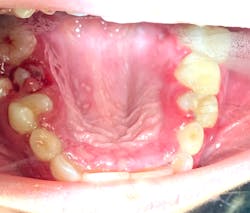

Note: The pictures are not of the highest quality as the patient was in extreme discomfort when I took them.

Definitive diagnosis is likely one of two: Herpangina or acute primary herpetic gingivostomatitis

The saying “nothing is for certain unless it’s in a petri dish” stands true in all pathology cases, including this one. However, based on the symptoms and clinical presentation, I was able to surmise that it was more than likely either herpangina or APHG, although I’m leaning toward APHG.